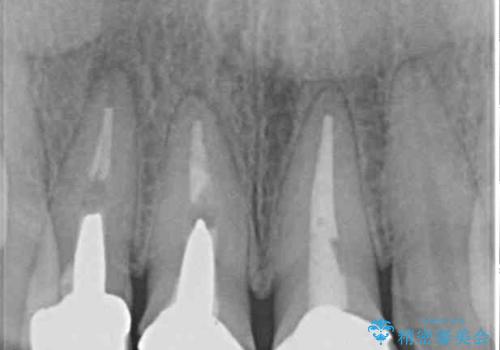

前歯は一部根管治療を行った後にオールセラミッククラウンに補綴することとしました。

補綴治療に先立ち、下顎前歯の部分矯正を行い、前歯の咬み合わせの安定性向上を図りました。

当初は上顎の補綴治療のみを希望されていましたが、仮歯装着期間に上下の前歯の接触が気になったため、部分矯正を行うこととしました。